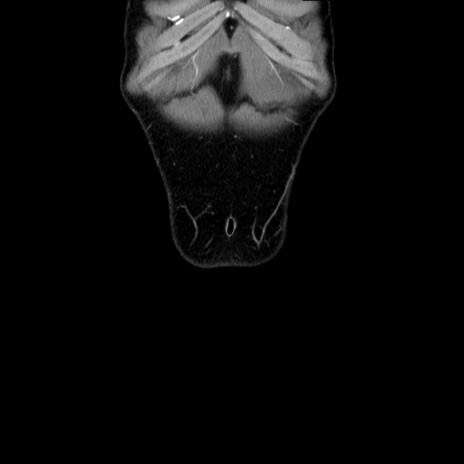

横断像